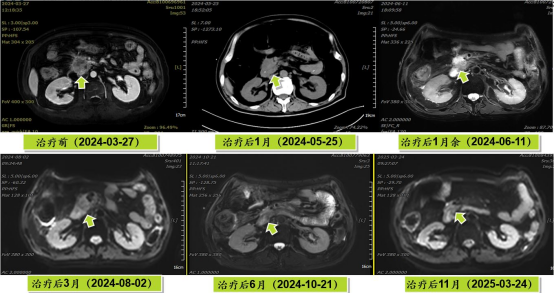

病例展示三:胰腺癌

腺癌病灶压迫并侵润十二指肠,十二指肠梗阻不能正常进食,患者留置营养管及胃肠减压管;伴胆道梗阻诱发黄疸,留置PTCD引流管。诊断:1.胰头恶性肿瘤 cT4N0M0 III期 KPS评分:80分;2.十二指肠不全梗阻;3.梗阻性黄疸,4.心律失常 室性期前收缩5. 慢性心力衰竭6.陈旧性心肌梗死7.冠状动脉粥样硬化性心脏病8. 缺血性心肌病。治疗:2024-05月开始吉西他滨+白蛋白紫杉醇化疗4周期,碳离子放疗剂量:PTV 36Gy(RBE)/9fx,后缩野补量,剂量:PTV boost 18Gy(RBE)/4fx,4.5Gy(RBE)/fx。

疗效评价